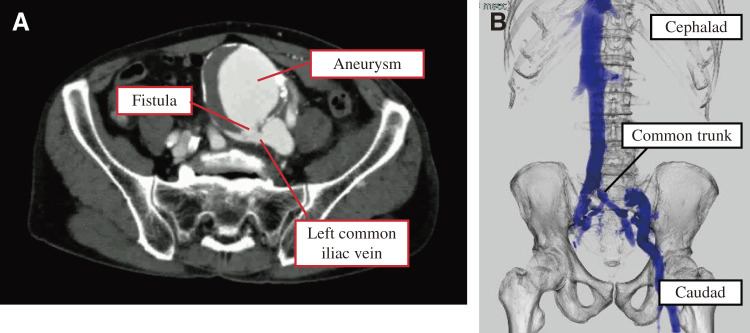

髂动脉动脉瘤破裂是一种严重的疾病,死亡率很高,偶尔会穿孔进入静脉系统。73岁男性,左腿水肿,左下腹部搏动性肿块。计算机断层扫描显示左侧髂总动脉瘤破裂并穿孔至左侧髂总静脉。此外,双侧髂内静脉形成异常总干,流入左侧髂总静脉。治疗包括透视下髂内静脉球囊闭塞,随后开放手术进行人工移植物置换和瘘管修复。患者于术后第8天出院。

Ruptured iliac artery aneurysms are serious conditions with high mortality, occasionally perforating into the venous system. A 73-year-old male presented with left leg edema and a pulsatile left lower abdominal mass. Computed tomography revealed a ruptured left common iliac artery aneurysm with perforation into the left common iliac vein. Additionally, bilateral internal iliac veins were noted to form an anomalous common trunk draining into the left common iliac vein. Treatment involved internal iliac vein balloon occlusion under fluoroscopy followed by open surgery for artificial graft replacement and fistula repair. The patient was discharged on the 8th postoperative day.